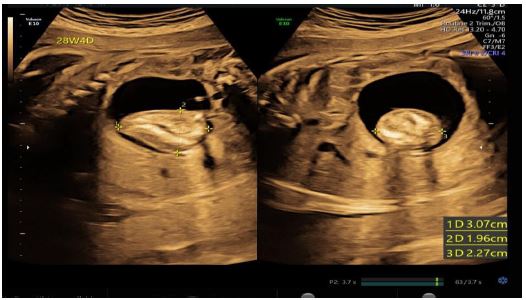

A 28-year-old pregnant woman, gravida 2 para 1 abortion 1, presented to our department with an abnormal ultrasound scan at 22 weeks’ gestation that revealed a fetal abdominal mass. Initially this was thought to be a teratoma. Family history was negative for congenital malformations, and there was no history of medication and drug use during pregnancy. Upon detailed sonography scanning in our institution a 25 mm in diameter heterogeneous abdominal mass with an internal density mass was visualized. The mass was well circumscribed and power doppler investigation revealed normal blood flow. Monthly repeat studies showed the mass steadily enlarging. A formal follow-up ultrasound at 26 weeks gestation demonstrated that the mass was 38 mm in diameter with rudimentary spine, ribs, ilium and a limb. A subsequent magnetic resonance imaging verified the heterogenous mass with multiple bones and vertebral body. At this stage an endoparasitic FIF was diagnosed. Amniocentesis that performed at 23 weeks’ gestation demonstrated a normal karyotype and testing of maternal alpha-fetoprotein levels was not performed. The boy was born full term by normal vaginal delivery with a birth weight of 3080 g. He had Apgar scores of 10 and 10 at 1 and 5 min, respectively. At laparotomy shortly after birth an encapsulated retroperitoneal mass was resected. Gross anatomy and pathological examination demonstrated a fetus in fetu, as well as DNA fingerprinting techniques confirming identical genetic material shared by the child and the mass. From the gross anatomy the lower part of body with a limb and an umbilical cord could be seen. The baby did well postoperatively.

Figure 1: Prenatal ultrasound examination of the FIF at 26 weeks’ gestation (left) and 22 weeks’ gestation (right).